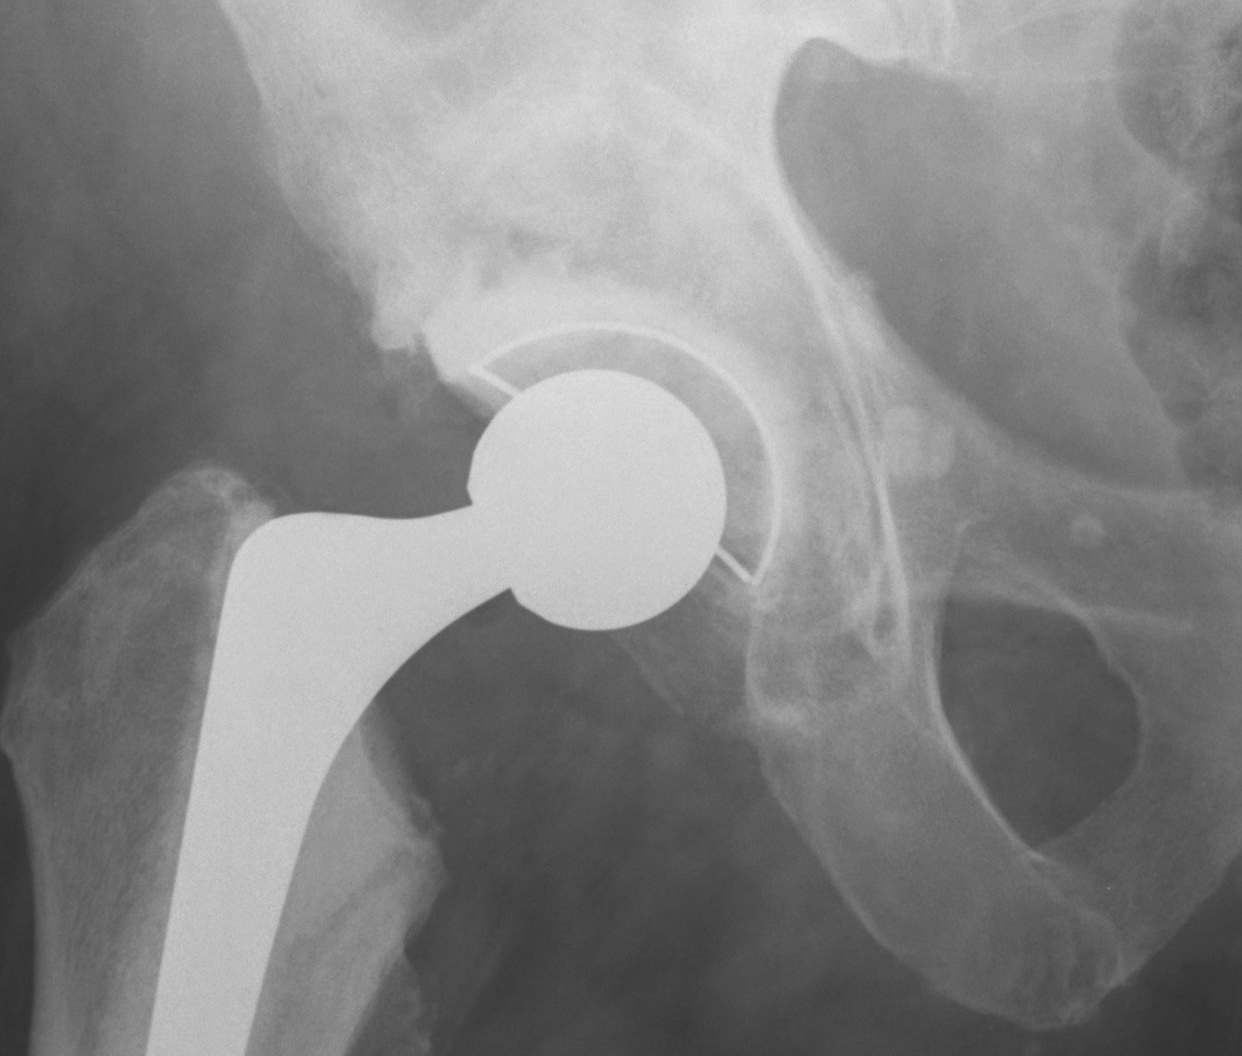

1. Uncemented Jumbo rim fit cup

Indications

- > 50% host bone available for ingrowth

- > 2/3 rim intact

Technique

- implant in usual position

- preferentially ream anteriorly

- preserve posterior column

- some uncovering superiorly allowed

- usually augment with screws

- +/- postoperatively NWB 6/52

Results

- 12-15 year survival between 81-96%